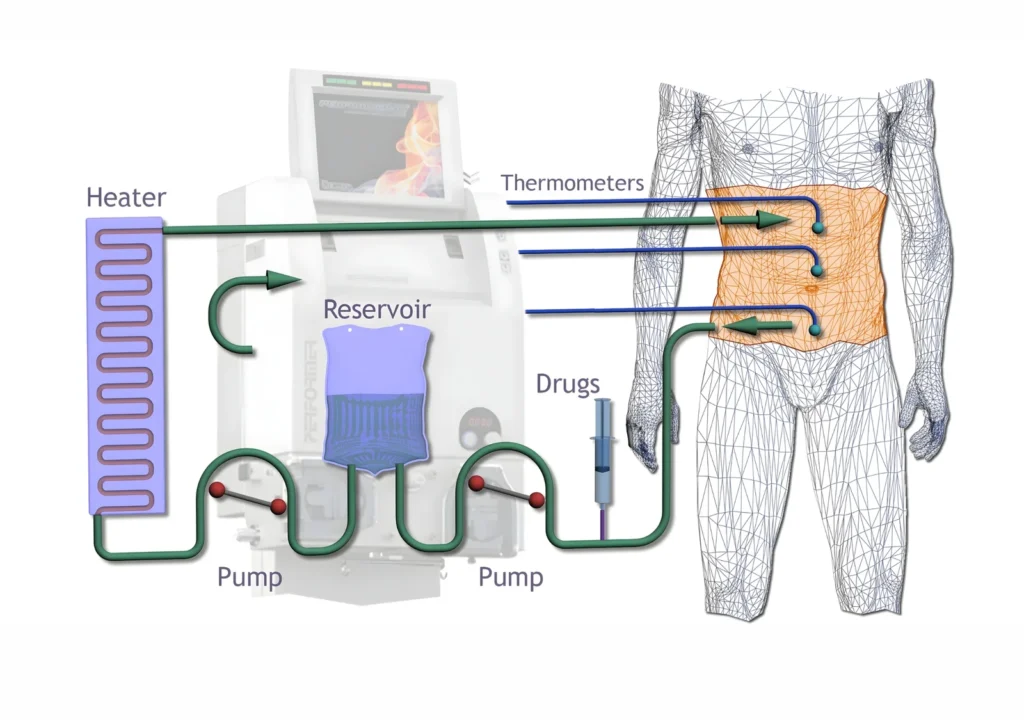

Heated Chemotherapy Circulation

Chemotherapy solution heated to 41–43°C

Circulated within the abdomen for 60–90 minutes

Continuous movement ensures uniform drug distribution

Heat enhances chemotherapy effectiveness by damaging cancer cells and increasing drug penetration.

Targeted Local Therapy Advantage

High local drug concentration at tumor sites

Limited systemic absorption and toxicity

Improved effectiveness against microscopic residual disease